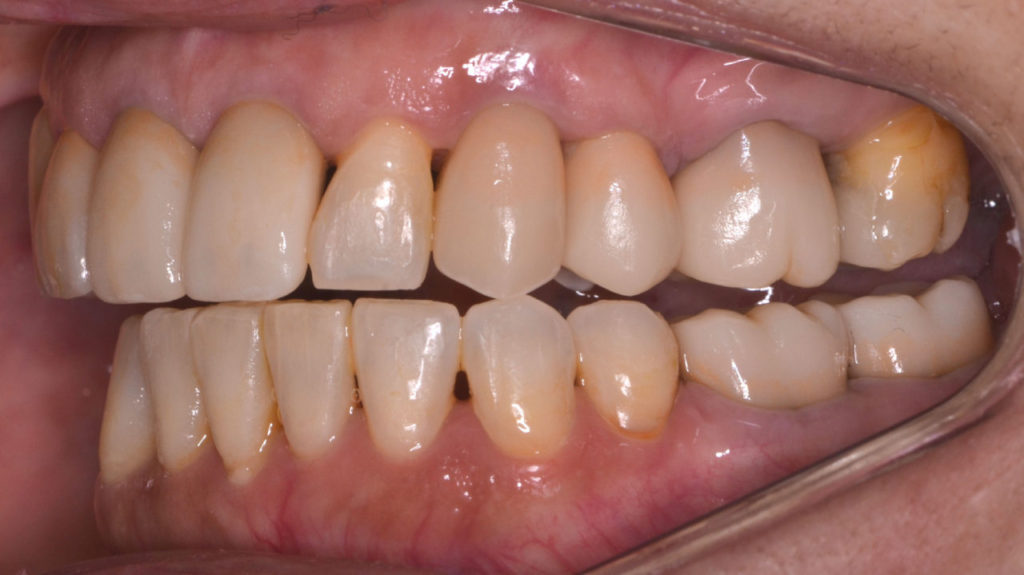

治療前

奥歯が干渉している状態

治療後

矯正を伴う咬合再構成を行った患者さんです。アンテリア ガイダンスが取れるようになりました。